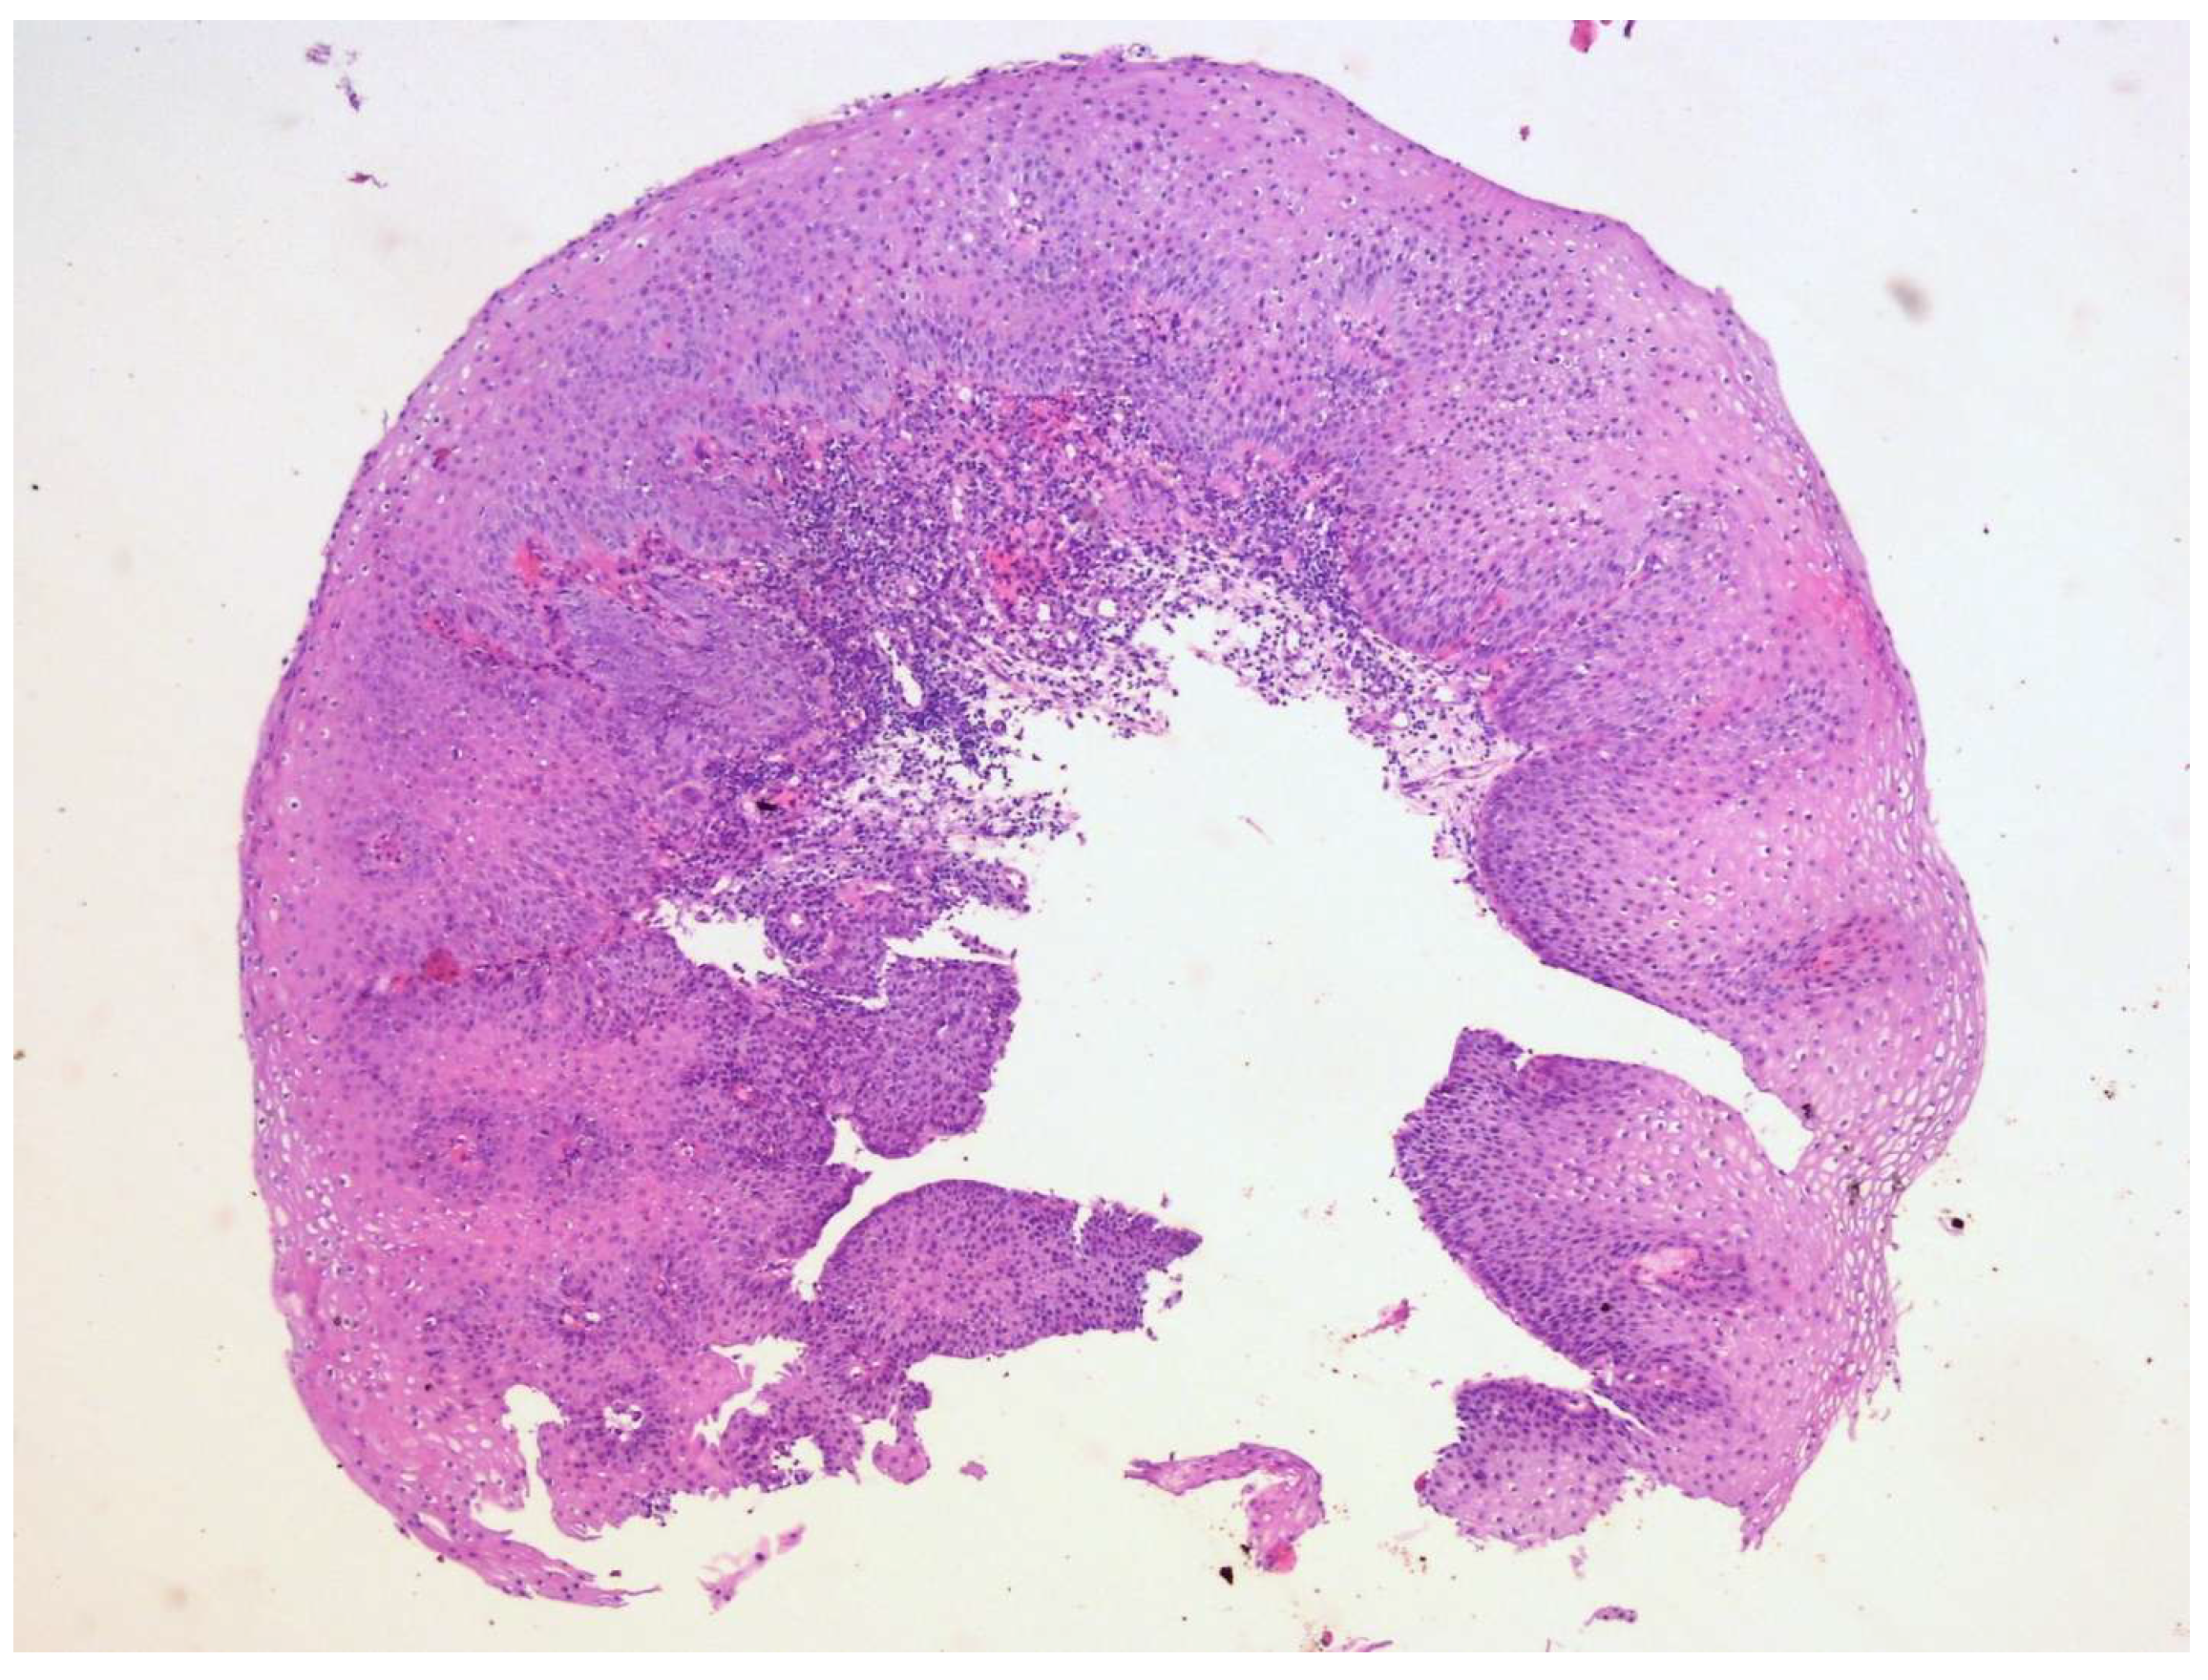

Figure 9. During control endoscopy, biopsies were taken from the tissue covering the coil itself. A regenerative zone of the mucosa was observed with reactive changes in the squamous cell epithelium, and another sample showed remnants of granulation tissue (HE, magnification 10×). The patient was discharged one month after the coil placement, in good general condition, with normal peroral feeding. No symptoms or complications related to the fistula were present at the moment of discharge from the hospital. In conclusion, the management of TEF requires prompt intervention to prevent serious complications that this condition carries along. Surgical repair remains the gold standard and is often the most effective treatment, particularly for larger or complex fistulas. However, in cases where surgery is contraindicated or not feasible, a variety of non-surgical options, including stenting, endoscopic techniques, tissue adhesives, and occluding devices are available. Given the limitations and variable success rates of these alternatives, treatment should be carefully individualized based on patients’ clinical condition, fistula characteristics, and overall prognosis.